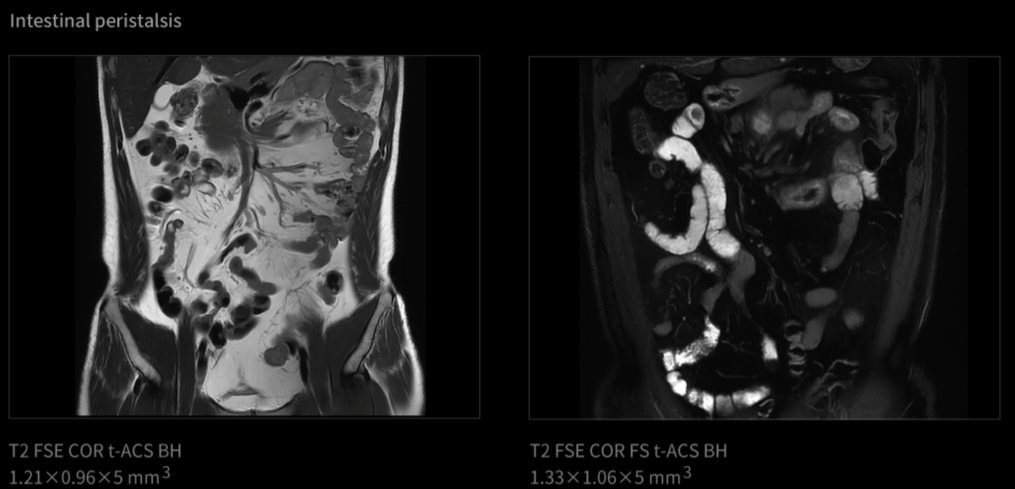

Od vzniku magnetické rezonance je pohyb jednou z největších výzev při zobrazování. Celá desetiletí byly v tomto odvětví zkoumány různé technologie pro „zmrazení pohybu“. Inovace uMR Ultra dnes slibuje svět MRI bez omezení pohybu – oblast, ve které můžeme pozorovat skutečný stav lidského těla. Jelikož otevíráme novou dimenzi zobrazování pomocí MR, je komplexní transformace diagnostických standardů nevyhnutelná.

UMR Ultra je vybaven nejmodernější technologií, která poskytuje výjimečné zobrazovací schopnosti a zaručuje přesné a konzistentní výsledky v širokém spektru klinických aplikací. Jeho pokročilý zobrazovací systém nabízí jasnost a přesnost od hlavy až po paty a tvoří základ spolehlivé diagnózy. Zařízení uMR Ultra, podporované nejmodernějším hardwarem a inovativním softwarem, zlepšuje klinické pracovní postupy a přispívá k průlomovým objevům i ke zlepšení péče o pacienty.